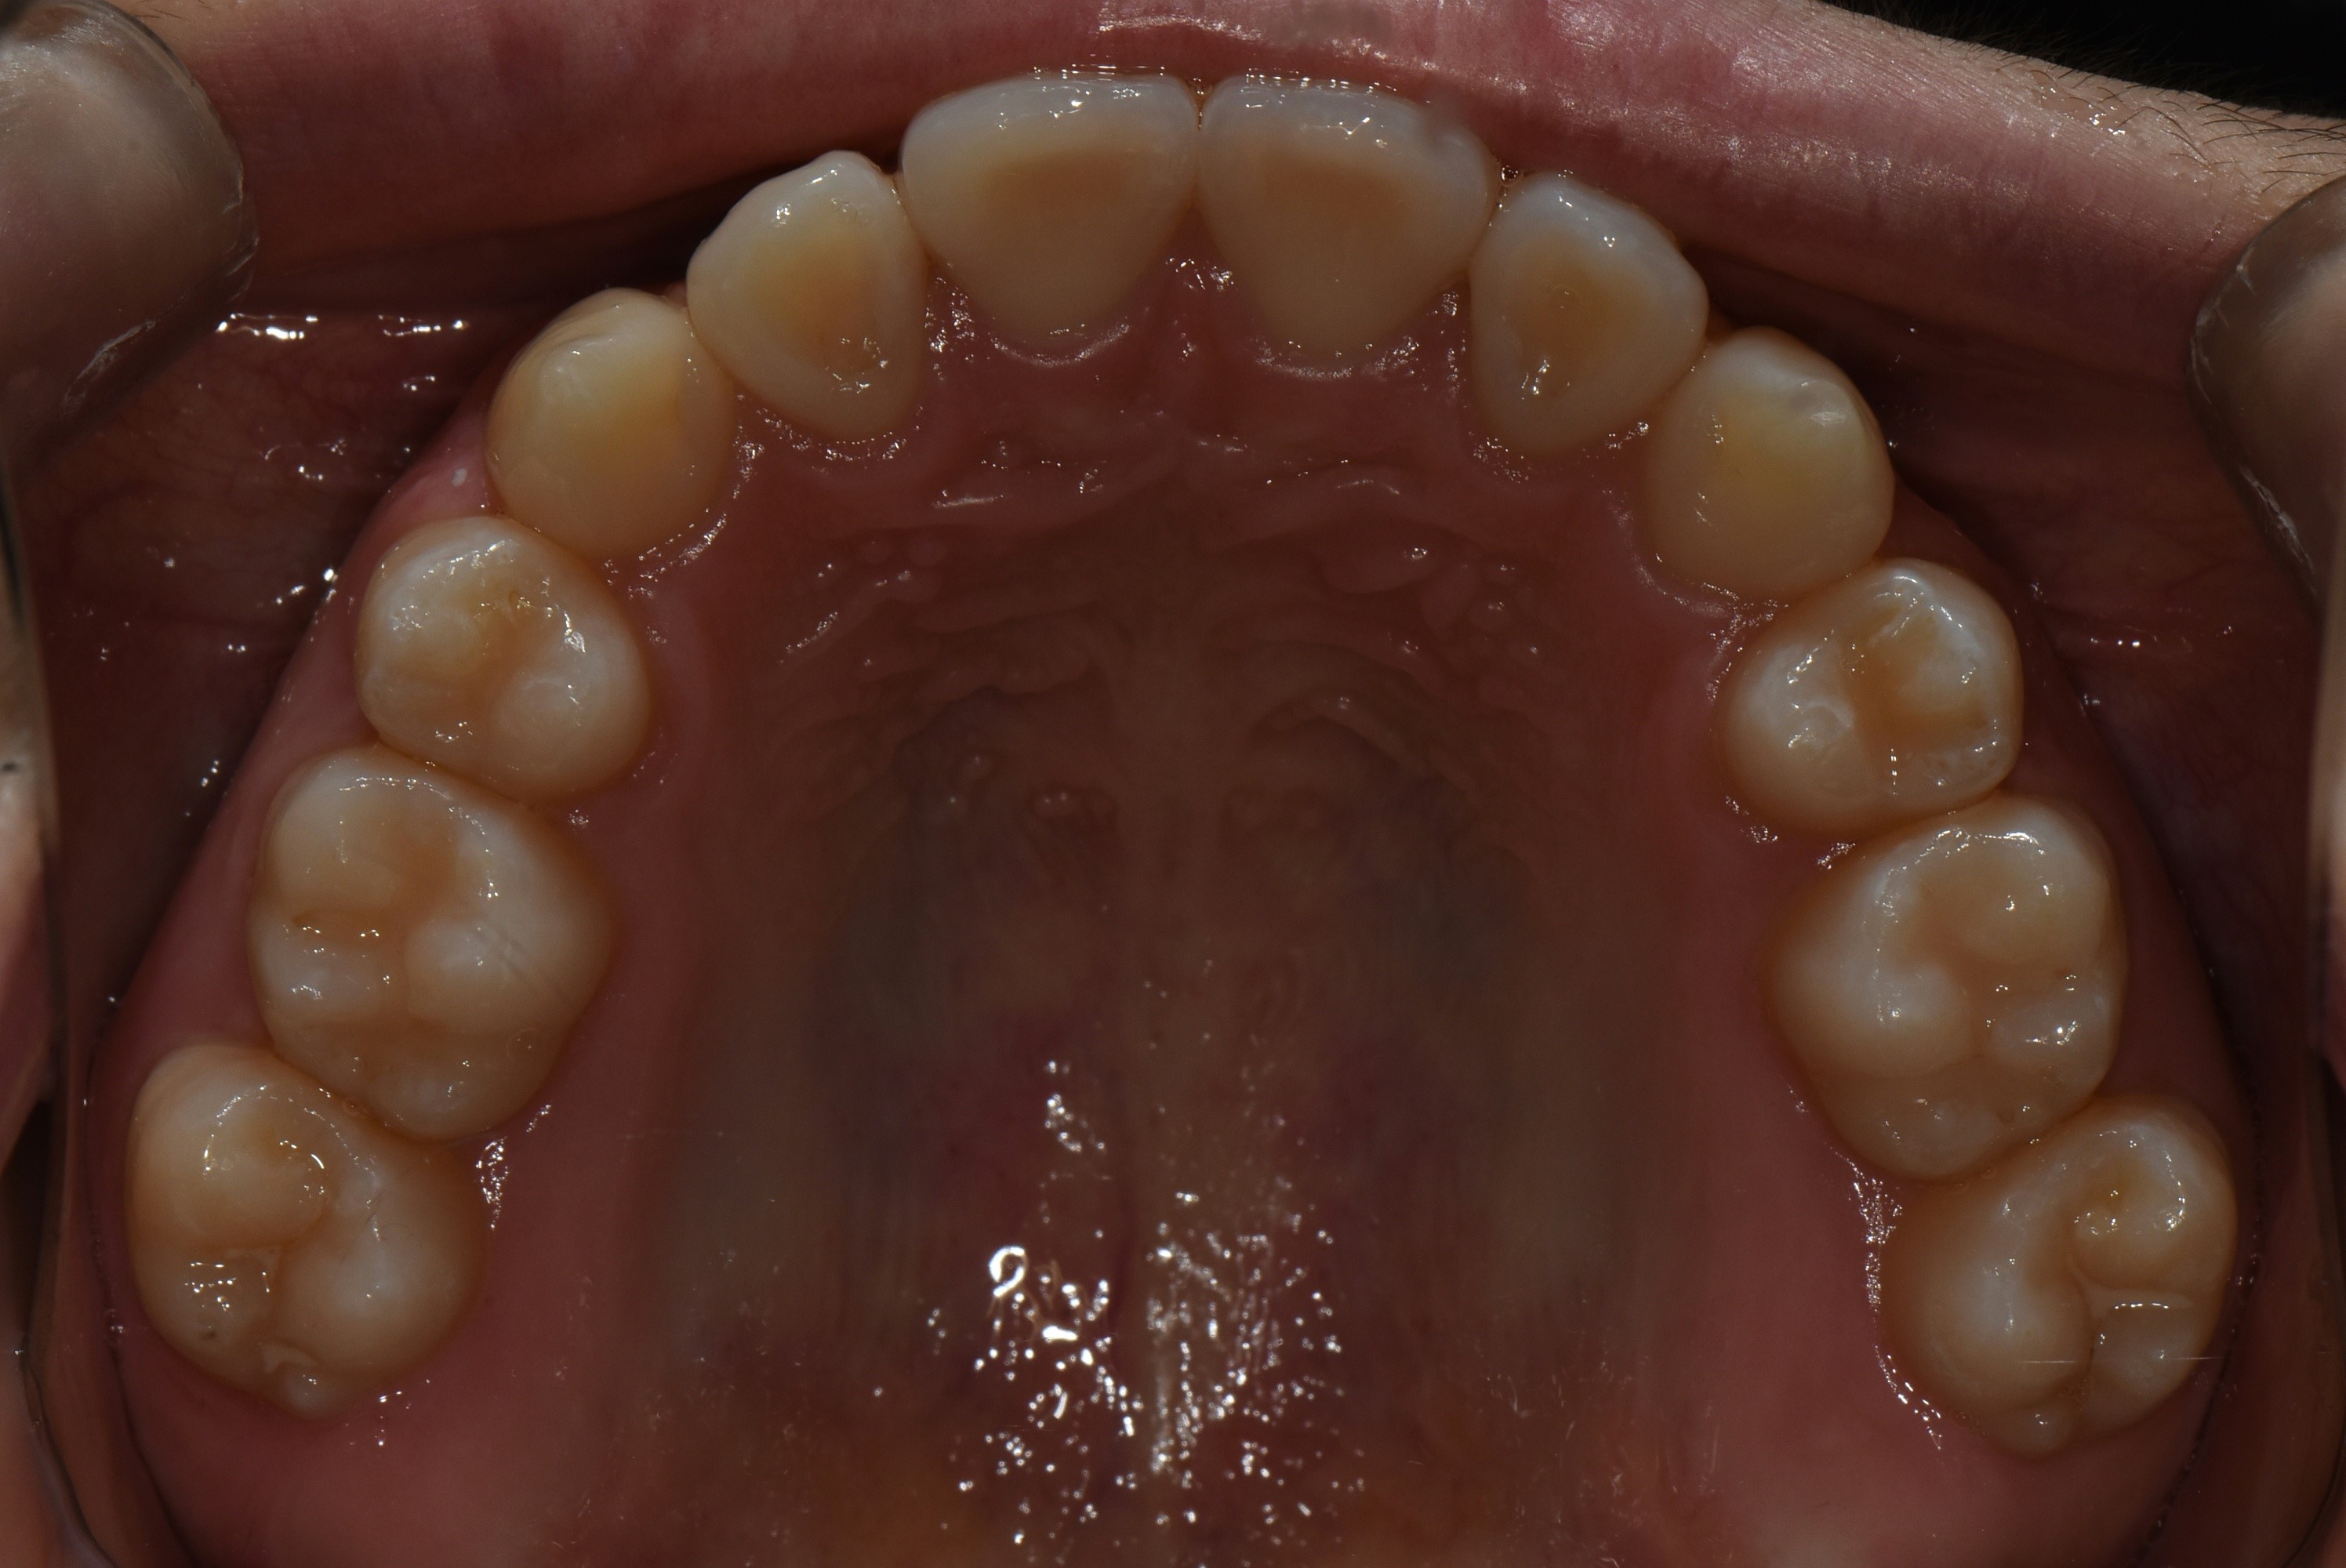

치료 후 사진입니다.